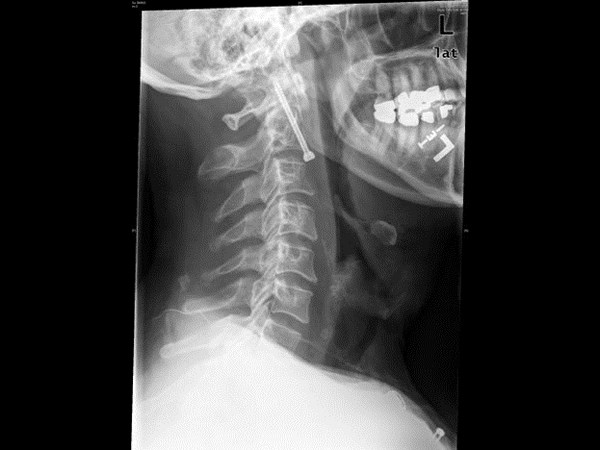

மருத்துவ உலகம் கண்டு வியந்த எக்ஸ் ரே படங்கள்

கழுத்தில் ஆணி உள்ளது.